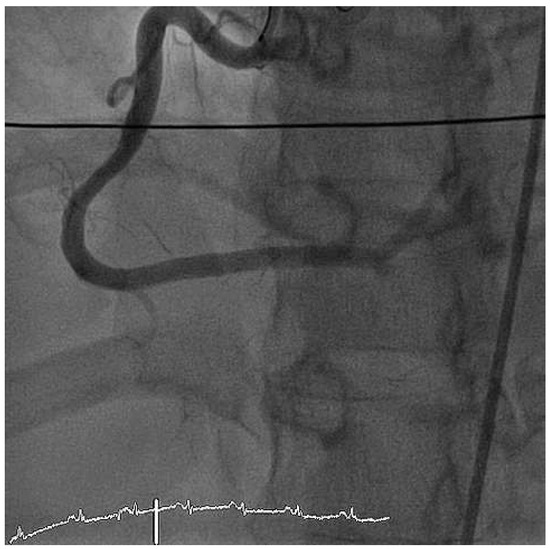

We report the case of a 47-year old man who presented with severe cardiogenic shock and signs of ST-elevation myocardial infarction. Urgent coronary angiography showed thrombotic occlusion of the mid left anterior descending artery (LAD) and the circumflex artery, as well as a [...] Read more.

We report the case of a 47-year old man who presented with severe cardiogenic shock and signs of ST-elevation myocardial infarction. Urgent coronary angiography showed thrombotic occlusion of the mid left anterior descending artery (LAD) and the circumflex artery, as well as a subtotal thrombotic occlusion of the right coronary artery without signs of relevant atherosclerotic coronary disease. The patient was treated with thrombus aspiration in all coronary vessels and PTCA of the LAD with good result. Despite thorough investigation of major nonatherosclerotic causes of myocardial infarction, which are further discussed in our case report, the case remains unsolved. Until today the patient is free of symptoms under long-term dual antiplatelet-inhibitor therapy. Full article